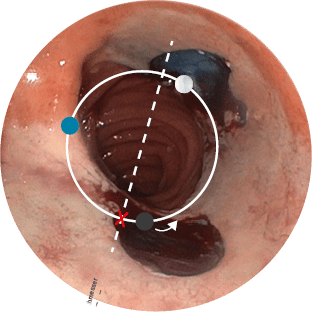

Positionsermittlung

Die korrekte Positionierung der BARS® Anchor ist entscheidend für eine erfolgreiche Behandlung.

- Mit einer gedachten Mittellinie die Anastomose in zwei Hälften teilen.

X = Austrittspunkt Endoskoparbeitskanal - Die Anchor knapp unterhalb der Mittellinie platzieren.

• = BARS® Anchor Black, • = BARS® Anchor Silver. - Der Kalibrierballon (•) definiert das Restlumen im gegenüberliegenden Halbkreis.

2Quelle: Prof. A. Schmidt, Universitätsklinikum Freiburg, Deutschland

Beispiel 1*

Anvisieren der Applikationsstelle.